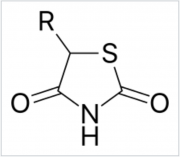

| 12:56, 4 בדצמבר 2017 | Thiazolidinedione1.PNG (קובץ) |  |

53 קילו־בייטים | Motyk | 1 | |